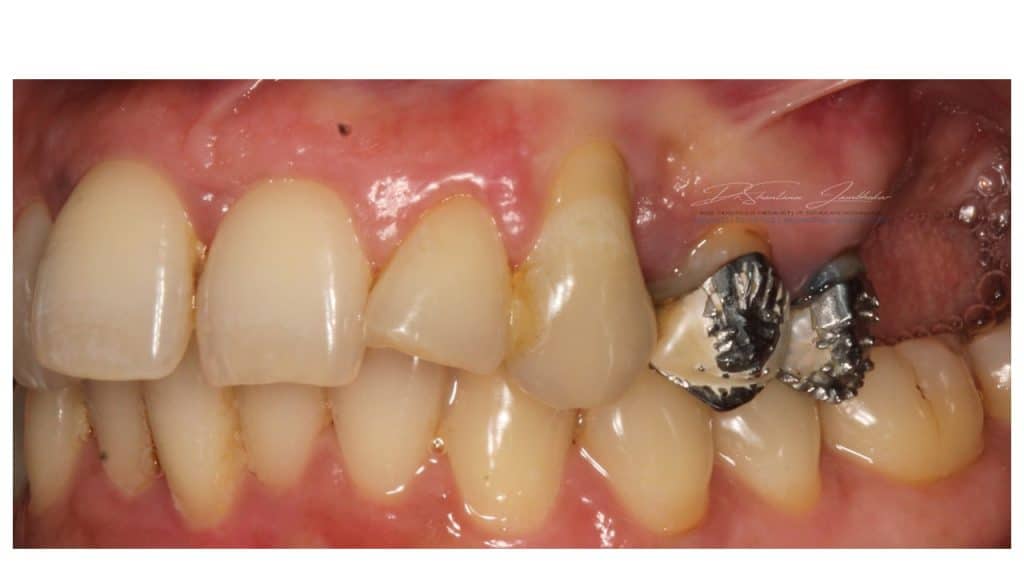

A 53 year old female patient reported to us with gingival recession, mobility with upper left canine, premolars & missing molar teeth and wanted fixed replacement of the same.

Intraoral examination revealed previous endodontic treatment with 23. Old splinted FDPs (24-25) with fractured ceramic facings H\o endodontic treatment. Grade 2-3 mobility was seen with these teeth. She also gave a H\o periodontal therapy around 3-4 years ago. No signs of active infection or sinus tract seen. Teeth 23,24,25 had poor prognosis and were deemed for extractions.

Pre-Treatment Baseline